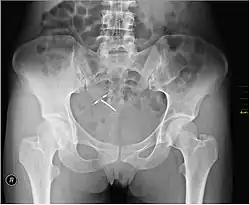

Regardless of the IUD type, some potential side effects are similar for all IUDs. Some of these side effects include bleeding pattern changes, expulsion, and pelvic inflammatory disease (especially in the first 21 days after insertion). The occurrence of IUD migration is rare, with reported rates in medical literature varying between 0.1% and 0.9%. However, when migration occurs, it can lead to serious complications such as uterine perforation and, in rare cases, bladder perforation. Bladder perforation, while uncommon (affecting only 2% of displaced IUDs), can result in symptoms like urinary frequency, hematuria, and stone formation, often necessitating surgical intervention for removal.[82] Regular monitoring and imaging, such as ultrasound or CT scans, are recommended to detect such complications early and ensure timely treatment. A small probability of pregnancy remains after IUD insertion, and when it occurs, there is a greater risk of ectopic pregnancy.[83]